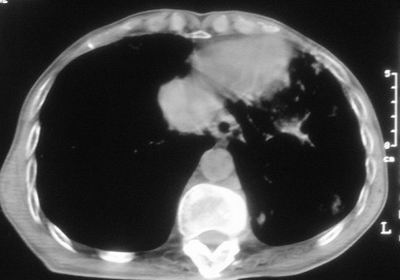

标题: CT11864:男,47岁,反复咳嗽、咯痰、咯血3年,请分析. [打印本页]

患者,男,47岁,反复咳嗽、咯痰、咯血3年,再发5天。痰培养未找到真菌、抗酸杆菌、癌细胞。

左肺上叶体积明显缩小,其内见多发透光区,纵隔向左侧移位,左肺下叶多发班片状病灶,边界模糊,1左肺上叶先天肺发育不全,2左肺下叶肺炎,

左肺上叶结核伴肺纤维化,纵隔移位,左肺下叶感染性病变,建议抗炎抗结核后复查,双肺气肿.

以下是引用xulianj在2008-2-25 21:01:00的发言:[br]左肺上叶结核伴肺纤维化有霉菌球形成,纵隔移位,左肺下叶感染性病变,建议抗炎抗结核后复查,双肺气肿.

考虑:左肺慢纤伴霉菌球形成、双肺全小叶型肺气肿。

1)考虑为:左肺上叶肺结核(空洞形成),伴左下肺感染;不排除霉菌感染可能。2)肺气肿。

左肺上叶结核伴肺纤维化空洞形成并左肺下叶感染,纵隔牵拉移位,建议作进一步检查排除左侧肺霉菌感染可能。